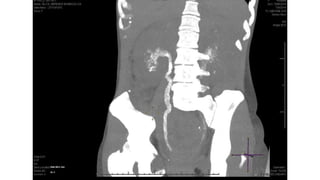

 TUBERCULOSE PULMONAR

 EXTRA PULMONAR

 Pleural

 Linfonodal

 Intestinal

 Hepatoesplênica

Renal

 Óssea

 SNC

 Cutânea

 Ocular

 Pericárdicaoneal.........